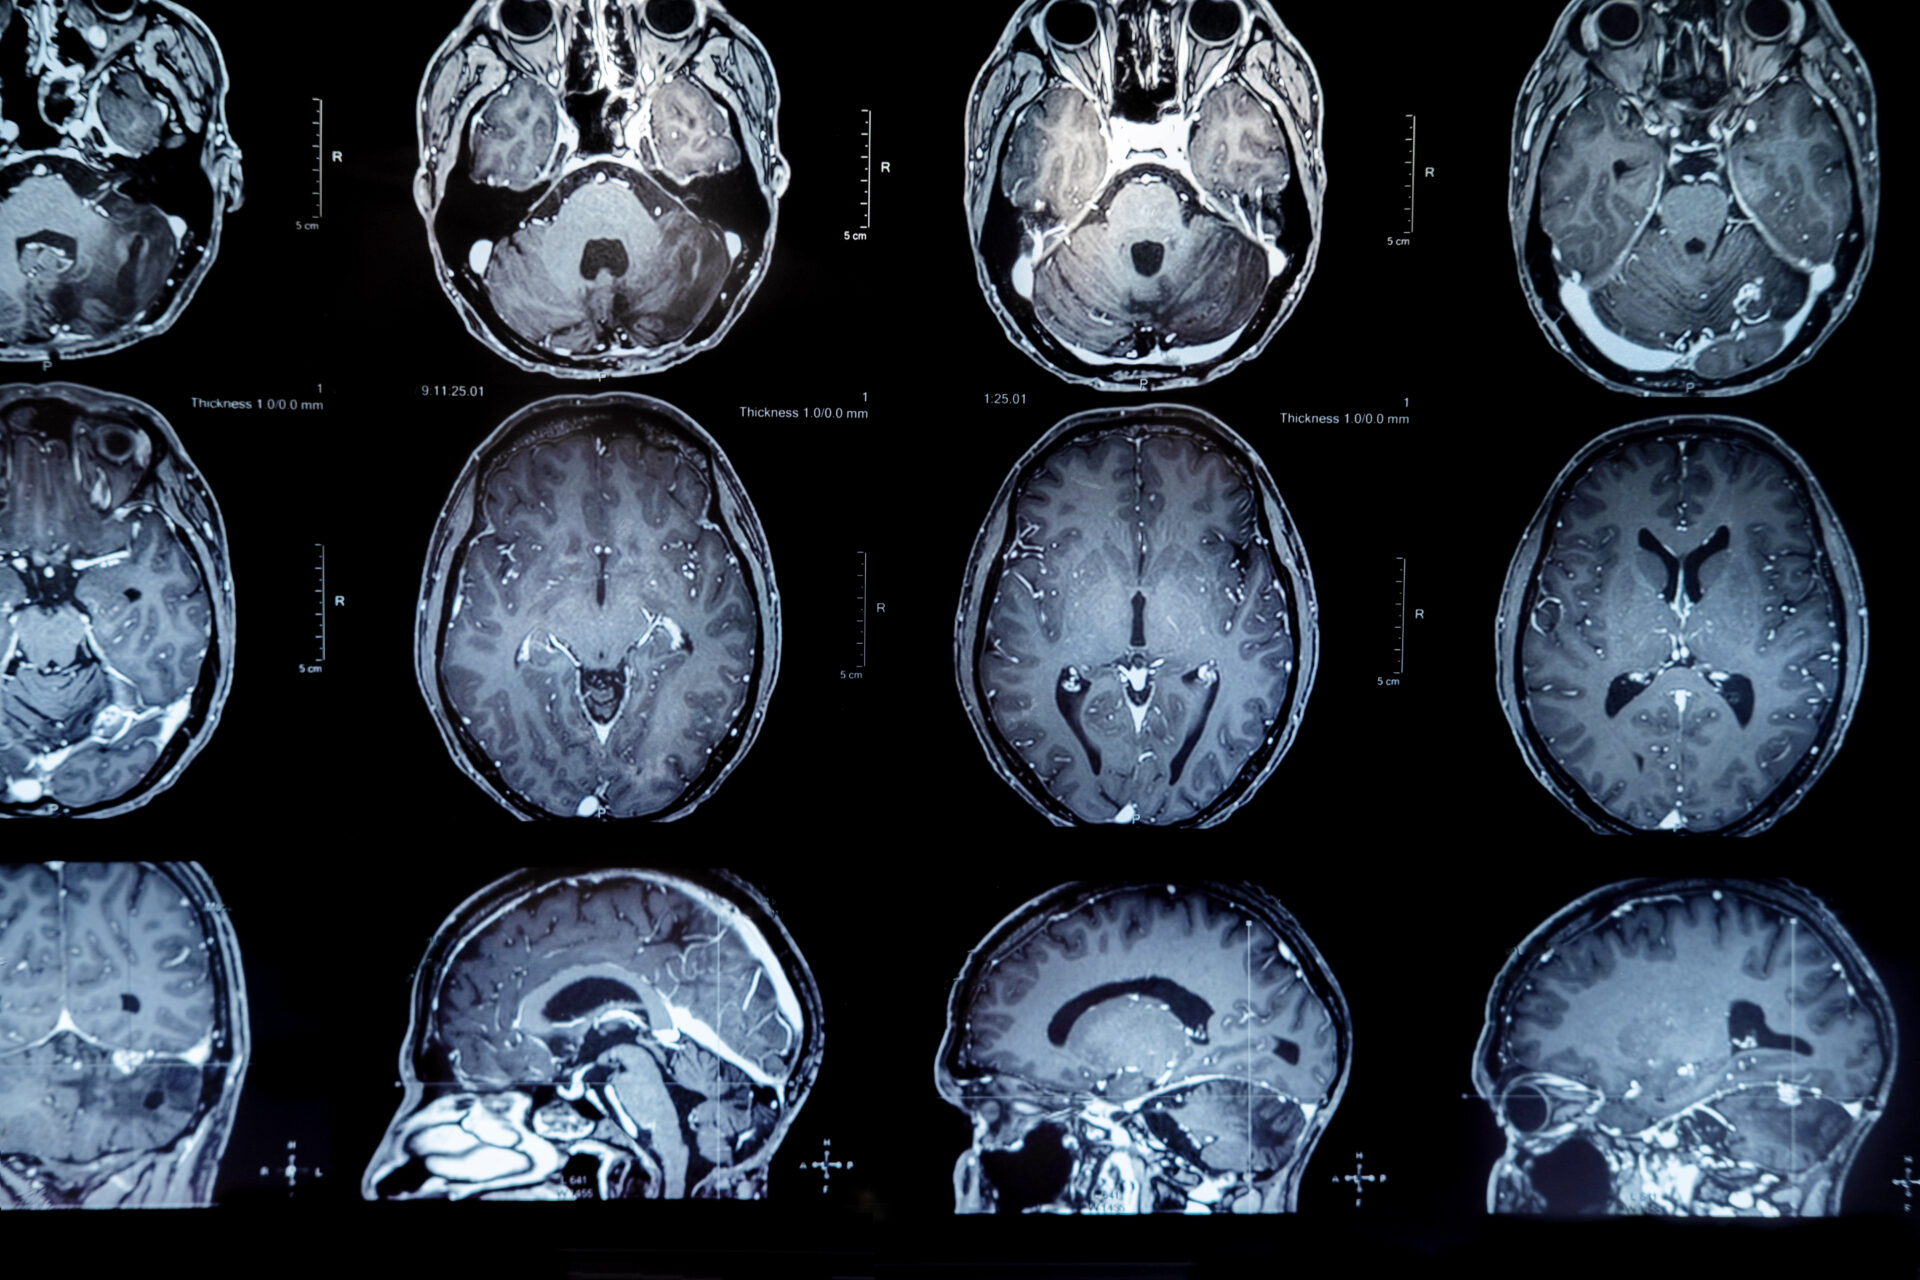

Là tình trạng tăng thể tích của não do tăng thành phần nước trong não. Phù não sẽ làm giảm tỷ trọng của não trên phim chụp cắt lớp vi tính sọ não. Phần não bị phù chủ yếu là phần chất trắng (chiếm khoảng 68% não), còn phần chất xám ít khi bị phù do bản chất đặc hơn.

MRI với khối u não – Chụp cộng hưởng từ.